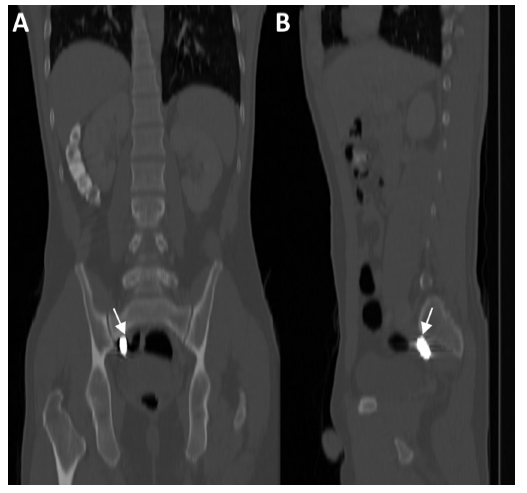

A 31-year-old man with no previous medical history was taken to the emergency department after suffering multiple injuries from a firearm, a chest wound and two in the right upper extremity, at a distance of approximately 8 meters, the gun caliber is unknown. The patient was alert, oriented with Glasgow 15/15 coma scale, normal vital signs, central and peripheral pulses, strong and symmetric, hemodynamically stable and negative shock index. The physical examination showed wounds with an entrance and exit hole in the proximal third of the right upper limb, another entrance and exit hole at the level of the hand of the same extremity. An entrance orifice was identified in the right deltoid region, without exit orifice. No wound had hard or soft signs of vascular injury. The initial chest radiograph shows a projectile in the right cervicothoracic region, without other findings (Figure 1). At six o'clock a new chest X-ray is performed, in which the projectile is not observed in the initial position (Figure 2). Radiography of the neck is performed, where the absence of the projectile is verified in the cervicothoracic space (Figure 3), but the abdomen radiograph shows the projectile in the right iliac fossa Figure 4(A,B). The follow-up with computed tomography without and with contrast of abdomen and pelvis showed the projectile lodged in right internal iliac vein (Figure 5). A grayscale and Doppler ultrasound study of the neck showed a small hematoma in place where the projectile was initially lodged without clearly demonstrating the path of communication with the right jugular vein by ultrasound. Because the patient was asymptomatic, the decision was made to treat the patient conservatively. After 2 years of follow-up, the patient remains asymptomatic.

Figure 4(B) CT of the abdomen in the bony window, coronal (A) and sagittal (B). A projectile (P) lodged in the right internal iliac fossa is observed at the level of the Sacral 1 vertebra. In the CT of the abdomen in the venous phase (not shown), the projectile was identified in the right internal Iliac vein.